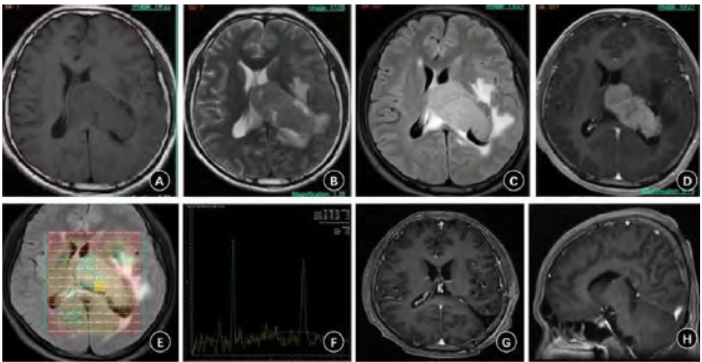

入院后头颅MRI平扫+T2 Flair+增强检查(图1A~D)示左侧侧脑室体部及体后部一巨大卵圆形囊室混杂团块影,实性部分为主,实性部分呈等T1、稍长T2信号影,囊性部分呈长T1、长T2信号影,增强后实性部分明显强化,囊性部分无强化,病灶主体位于脑室内,大小约7.0 cm×3.0 cm×3.0 cm,部分病变凸向右侧侧脑室体部,邻近左侧颞叶及顶叶受压,考虑左侧侧脑室脑膜瘤

可能。

入院头颅MRS显示病灶内Cho/NAA、Cho/Cr值增高,最高值分别约50.3、8.27,NAA峰低平,提示左侧侧脑室肿瘤,脑膜瘤可能(图1E、1F)。

图1 左侧侧脑室尤文肉瘤手术前后影像表现。A、B. 术前头颅MRI平扫显示做侧脑室混杂T1、T2信号影;C. 术前头颅MRI T2 Flair显示左侧侧脑室等高信号类圆形占位,伴周边水肿

;D. 术前头颅MRI增强显示左侧侧脑室病灶实体部分明显强化;E、F. 术前头颅MRS显示Cho/NAA明显升高,提示恶性肿瘤病变;G、H. 术后3个月头颅MRI增强扫描肿瘤切除满意,未见肿瘤复发征象